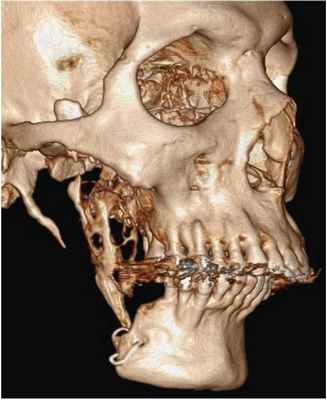

46-летний пациент обратился за помощью в частную стоматологическую клинику с жалобами на припухлость в области предварительно проведенной операции, охватывающей участок нижней челюсти справа. По данным медицинской документации было установлено, что около 15 лет назад пациенту была проведена сегментарная резекция челюсти с дальнейшей аугментацией сформированного дефекта аугментатом из области ребер. Данных о гистопатологических характеристиках поражения в медицинской карте пациента указано не было. После проведения КТ-сканирования и ортопантомографии было обнаружено мультилокулярное рентгенпрозрачное поражение в области предварительно проведенного оперативного вмешательства (фото 1).

Фото 1: 3-мерная реконструкция КТ-скана, демонстрирующего рецидивирующую опухоль в области аугментата с поражением суставного отростка.